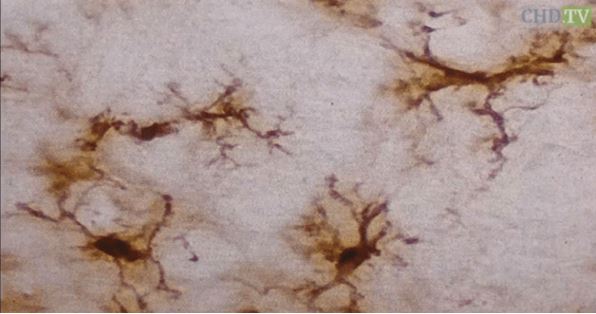

下の画像は、ミクログリアのさまざまな段階を表している。 画像の一番上にあるのは樹状ミクログリアで、これは「正常」であり、刺激を受けていない状態である。以前は「安静時ミクログリア」と呼ばれていたが、これは正確な表現ではない。  仮足は常に伸び縮みして、細胞外の空間に侵入者がいないか、化学物質の含有量が変化していないかなどを分析している、とブレイロック医師は説明している。

Photomicrograph of resting microglia

Photomicrograph of activated microglia